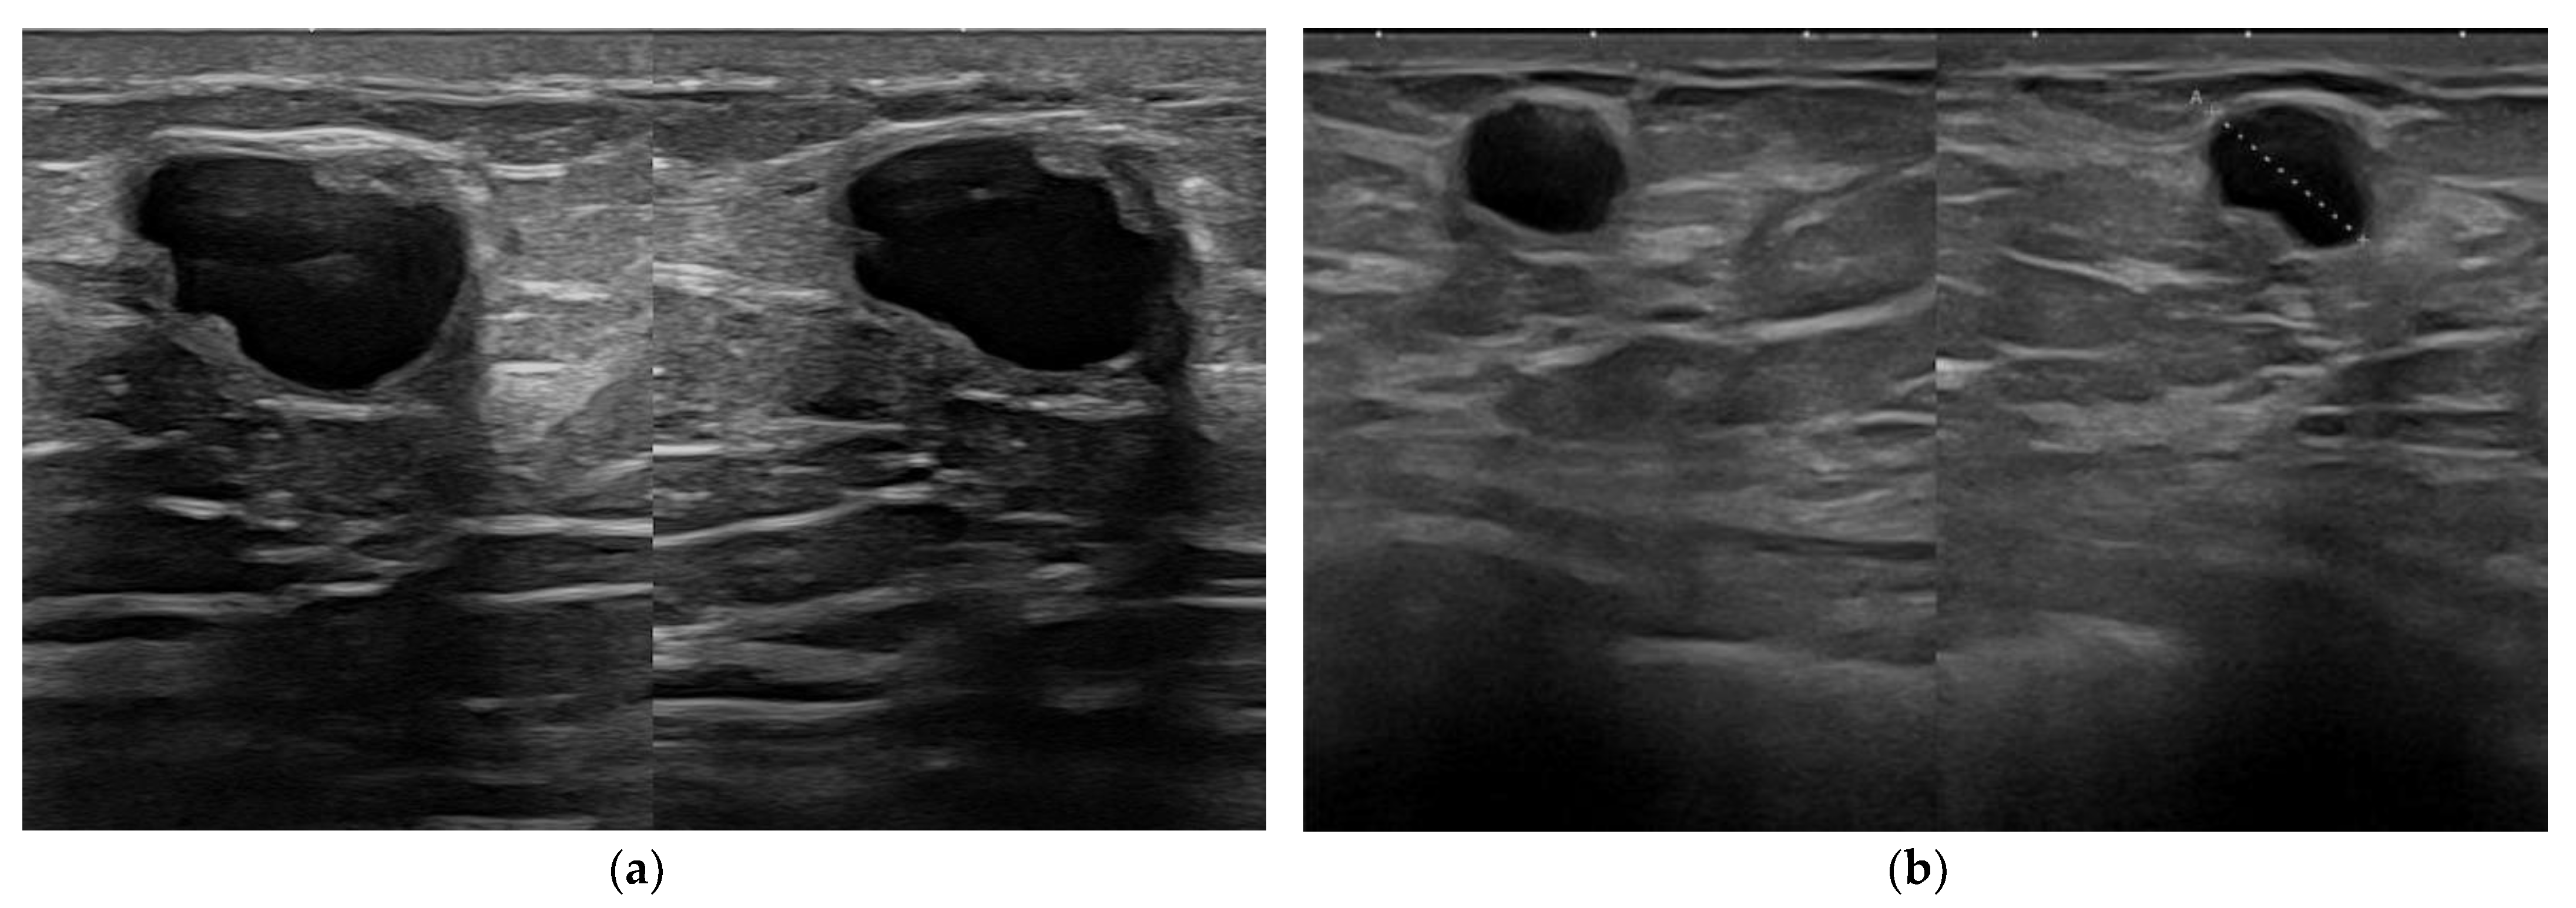

Figure 5. Ductectasia. Dilated ducts filled with dense, fluid material as they appear at 15 MHz (a) and at 22 MHz (b).